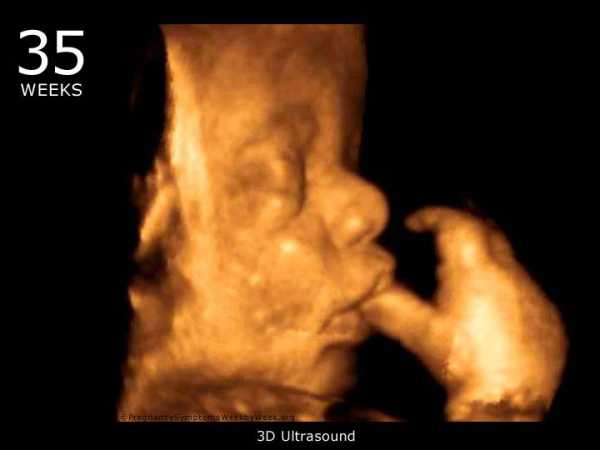

Определить, все ли нормально с плодными оболочками, исправно ли справляется со своей функцией плацента, нет ли каких угроз для малыша, поможет УЗИ на 35 неделе беременности. Как и прежде, при помощи ультразвука врач определит размеры плода и их соответствие сроку, оценит его сердцебиение, еще раз убедится в отсутствии каких-либо патологий и аномалий развития.

При проведении УЗИ обязательно берется во внимание качество и количество околоплодных вод, исключается риск обвития пуповиной. Проверит узист и степень зрелости плаценты: пока еще плацента находится во второй степени зрелости, но уже на следующей неделе перейдет в третью степень.

Еще раз будет подтверждено правильное предлежание малыша перед родами – головное. Если ребеночек так и не принял оптимального положения, будет рассмотрен вопрос о возможности родоразрешения путем кесаревого сечения.

Для контроля положения ребенка может быть назначено УЗИ на 35 неделе беременности. В том случае, если ребенок находится головой вверх, врачи будут выбирать тактику родов. В некоторых случаях показано кесарево сечение.

Проводя ультразвуковой скрининг, специалист обязательно обратит внимание и на положение пуповины. Тугое обвитие пуповиной может стать причиной гипоксии. Кроме того, при проведении УЗИ оценивается состояние плаценты, обеспечивающей связь материнского организма с плодом. На этом сроке нормальный показатель степени зрелости – второй.

Удостовериться в том, что малыш исправно готовится к рождению, поможет УЗИ на 35 неделе беременности. Если пол ребенка к этому времени еще неизвестен, то вы имеете шанс узнать его сейчас. Хотя далеко не все детишки показывают себя во время прохождения УЗИ, сохраняя интригу до самого рождения. Кроме того, на поздних сроках шанс увидеть заветное место снижается, поскольку малыш малоподвижен, и подолгу находится в одном положении.

Как обычно, специалист осмотрит ребеночка, оценит его главные параметры, двигательную активность, сердцебиение, состояние околоплодных вод, матки, пуповины, плаценты, степень ее зрелости. Сейчас плацента должна еще находиться во второй степени зрелости, а уже после 36 недели нормой будет считаться даже третья. Чем выше степень зрелости плаценты, тем меньшими остаются ее ресурсы. Впрочем, эти показатели нельзя воспринимать буквально, поскольку нередки случаи, когда после 40 недели беременности плацента еще довольно «молодая» или же отлично справляется со своими функциями, невзирая на свою «давность». Так что без дополнительных исследований окончательные выводы делать не стоит. Вот почему на 35 неделе также проводится допплерография.

УЗИ перед родами поможет врачу удостовериться в том, что никаких пороков и патологий в развитии ребеночка нет, и что он расположился правильно, то есть устремился головкой вниз. Если это не так, то врач может принять решение о проведении операции кесарева сечения. На это влияет целый ряд других факторов: вес и параметры роженицы, состояние ее здоровья, вес ребенка, степень обвития его пуповиной и прочие. Если вердикт гинеколога вас не утешит, то вы вполне можете проконсультироваться с другим специалистом. Однако не расстраивайтесь, если естественные роды окажутся для вас под запретом: решение всегда принимается в интересах матери и ребенка.